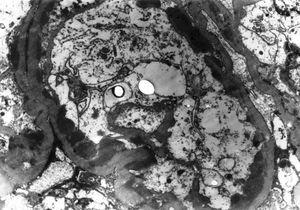

The two other groups of glomerular diseases for which the EM study was essential were the mesangiocapillary GN (MPGN) and the hereditary glomperulopathies. EM is essential for the accurate categorization of the subtypes of MPGN, as shown in Figure 2. Similarly, EM study is essential for the correct diagnosis of all cases of hereditary glomerular diseases.10 We found one case each of Alport’s syndrome (Figure 3) and tthin basement membrane disease (TBMD) in this series. It is interesting to note that TBMD typically does not cause NS, but occasional cases have been described with nephrotic range proteinuria.24 Additionally, the diagnosis of TBMD can not be based solely on morphological criteria, as many cases of Alport’s syndrome, can present with this phenotype. Genetic and pedigree analysis can resolve the differential in such cases. No family history was available of renal disease in our case and genetic testing could not be done due to non-availability of this facility.

Figure 3. Medium magnification view of glomerular basement membrane (GBM) showing focal thickening and rarefaction of the lamina densa of the GBM in a case of Alport syndrome.